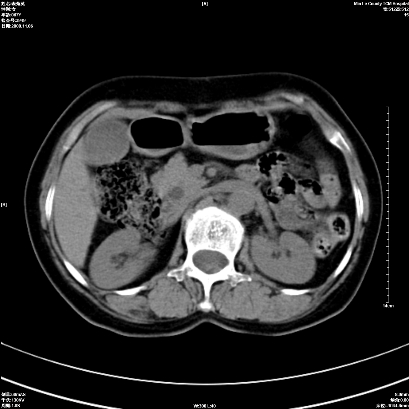

以下是引用卜一在2008-11-6 15:58:00的发言:[br]胰头略增大,胆总管扩张,末端渐行性狭窄。多考虑:胰头癌!建议增强!

以下是引用huangyinshan在2008-11-6 16:32:00的发言:[br]胰头略增大,胆总管扩张,末端渐行性狭窄。多考虑:胰头癌!建议增强!